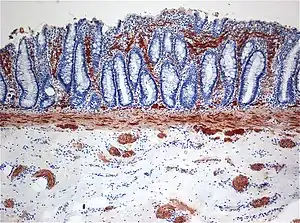

![]() | |

| Histopathology of Hirschsprung disease showing abnormal acetylcholine esterase (AchE)-positive nerve fibers (brown) in the mucosa | |